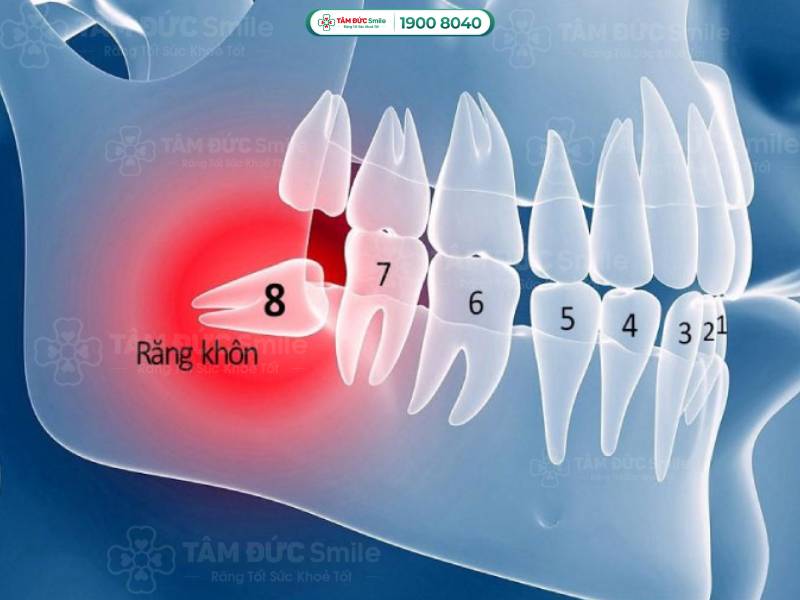

Vị trí và hình dáng của răng khôn

1.2. Răng khôn nằm ở vị trí khuất trong cung hàm

Tính từ ngoài vào trong, răng khôn nằm ở vị trí số 8 trong cùng của hàm. Vị trí này gây khó khăn cho bác sĩ khi phải đưa các dụng cụ nha khoa vào trong như tay khoan, mũi khoan, kìm nhổ răng,...

Răng khôn nằm ở vị trí số 8 trong cùng của hàm